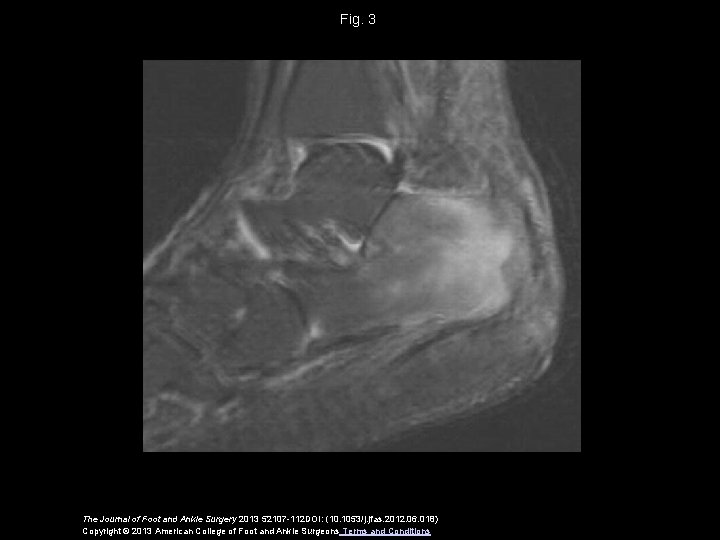

Fig. 3 The Journal of Foot and Ankle Surgery 2013 52107 -112 DOI: (10. 1053/j. jfas. 2012. 06. 018) Copyright © 2013 American College of Foot and Ankle Surgeons Terms and Conditions